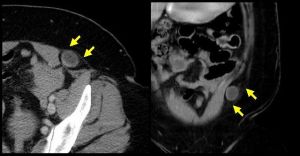

如果病人疝區的疼痛、腹壁包塊能被證實,尤其按壓疝塊能還納、並能觸及疝環孔邊緣,而且增加腹內壓的手法可使疝區疼痛加重時,則診斷幾乎沒有什麼困難。但由於缺損可能位於完整的腹外斜肌腱膜之下,疝塊形狀多數扁平、不易觸摸到或者包塊位於距半月線有一定距離的部位,因而診斷常常比較困難儘管單純的疝孔處壓痛並不足以做出診斷,但可提示其脫出部位(疝環或缺損所在位置),或多或少有助於診斷。B超和CT掃描可能有助於明確診斷。

B超和CT掃描可能有助於明確診斷。